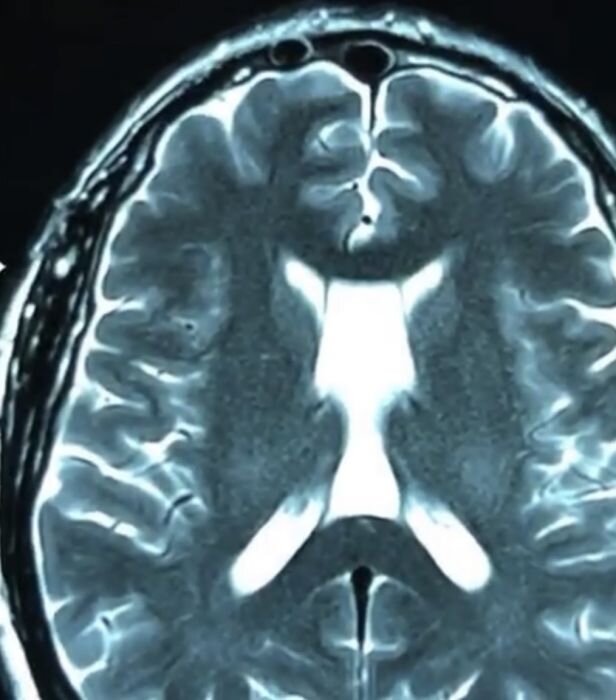

Арахноидальные кисты прозрачной перепонки головного мозга

Арахноидальные ретроцеребелярные кисты головного мозга